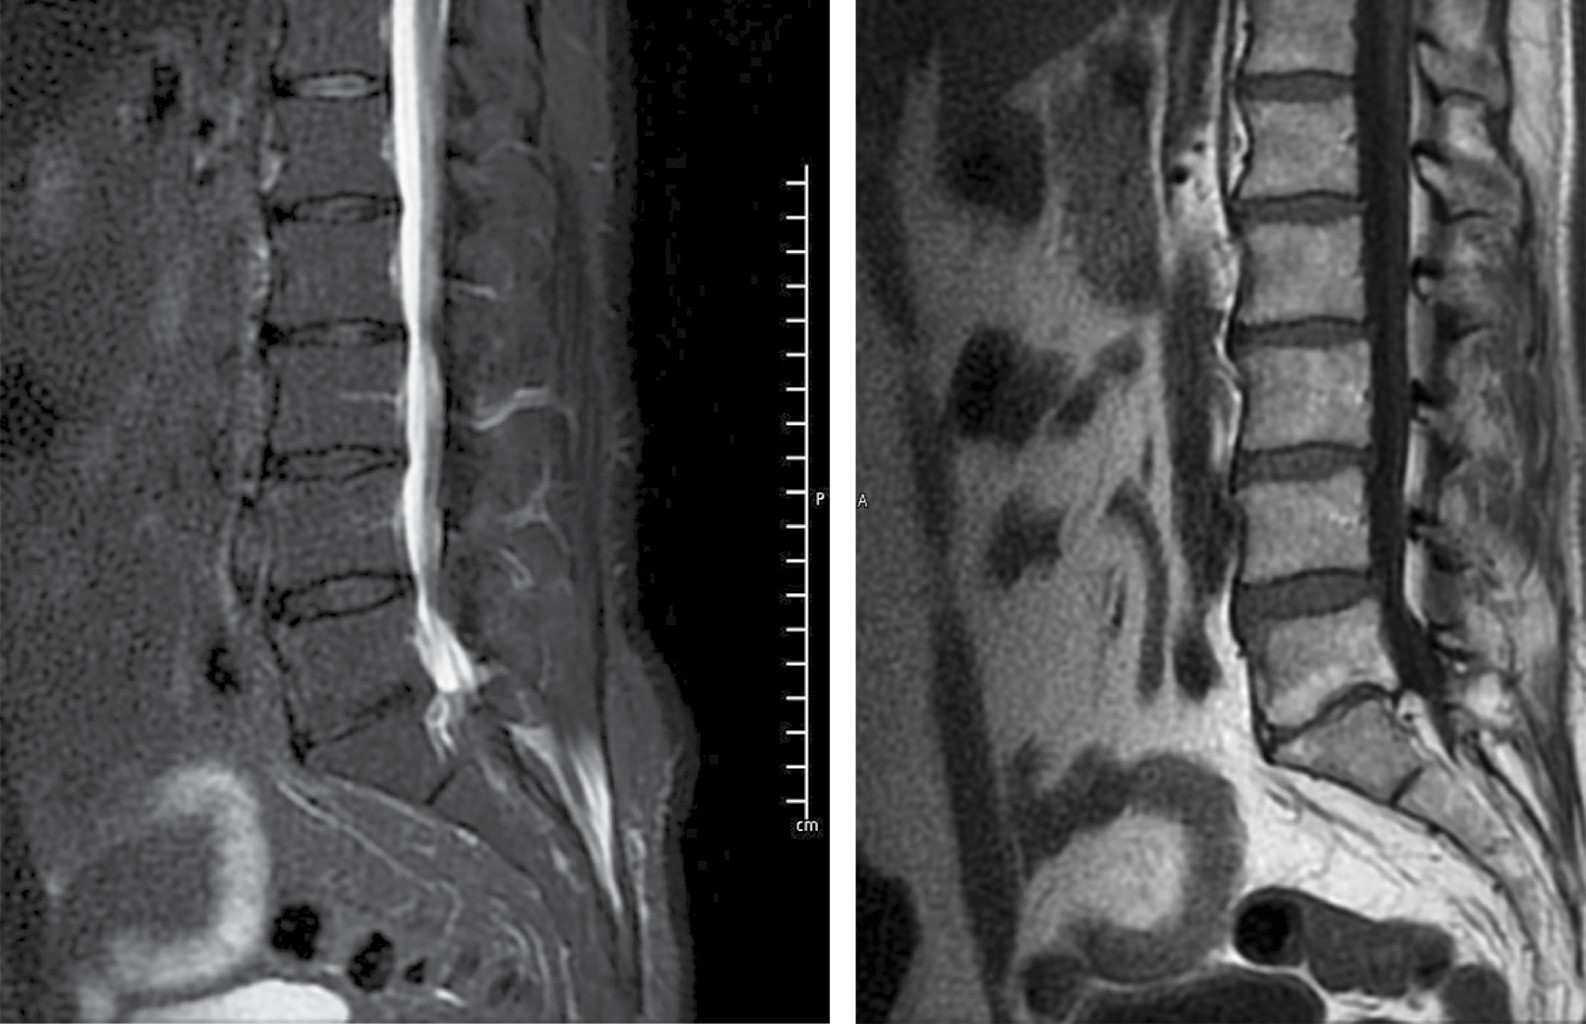

Los estudios de laboratorio en el postquirúrgico inmediato reportaron leucocitos de 14.8 × 103 cel/mm3 con 94% de neutrófilos, VSG de 54 mm/h y PCR 70 mg/l. El paciente reingresó para manejo del dolor en tres ocasiones, y en un estudio de imagen de seguimiento, con un mes de diferencia de la de ingreso, se evidenció la formación de abscesos paravertebrales (Figura 5). Posterior al tratamiento IV, se decidió continuar con trimetoprima/sulfametoxazol y doxiciclina por vía oral por dos meses más. El paciente respondió bien a la antibioticoterapia observando resolución de los abscesos en una nueva resonancia magnética dos meses después del inicio del tratamiento. Así mismo, durante sus reingresos y posterior a ellos, se estuvieron tomando estudios de laboratorio donde se evidenció disminución de los reactantes de fase aguda (PCR de 2.1 mg/l, VSG 26 mm/h).

Durante el seguimiento en la consulta, el paciente refiere mejoría del dolor, aunque presenta parestesias de la pierna ipsilateral desde la rodilla al tobillo siete meses después del procedimiento quirúrgico (Figura 6).